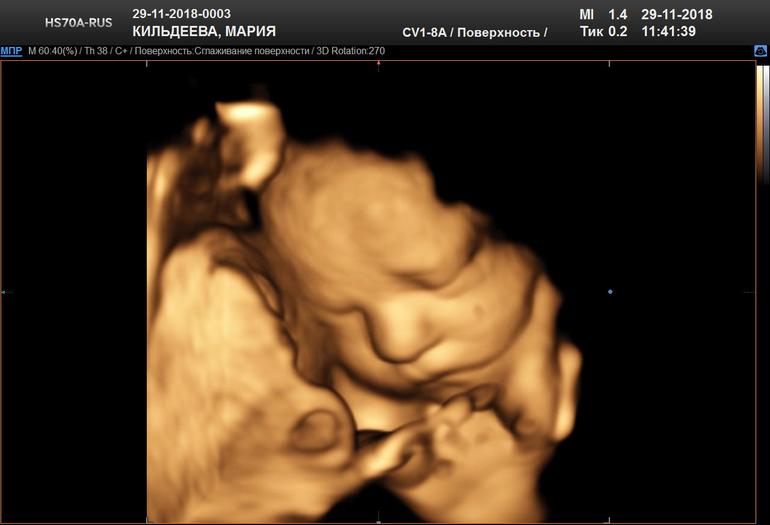

31 неделька и 3 дня,5d узи в Арт мед.

Сегодня съездили с мужем в медицинский центр на Красной пресне и сделали 5d УЗИ.Ну что я могу сказать,впечатления непередаваемые. У мужа с лица не сходила улыбка,это надо было видеть.😊

И сегодня нам уже на 100 процентов подтвердили девочку.Такая крошка милая,и пальчик на ноге сосала и улыбалась и ручками моську прятала.Дали диск с видео с комментариями врача,распечатали 10 фотографий,дали заключение и скинули цветные фото в программу Hello mom на телефон. Рекомендую Варламову Ольгу Леонидовну,чудесный доктор. Ну а теперь прошу ,знакомьтесь .Наша Елизавета Алексеевна.